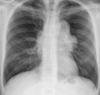

Pneumothorax